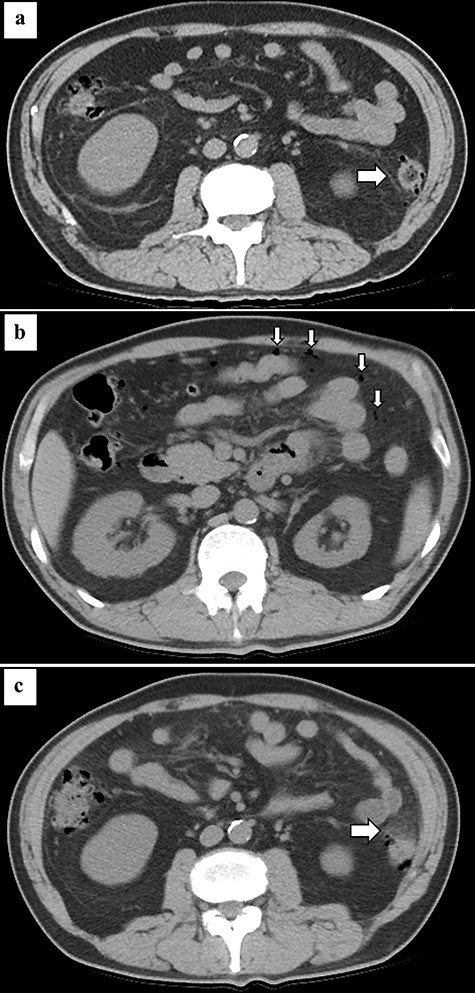

A 59-year-old man with a history of hypertension, type II diabetes mellitus, old myocardial infarction and chronic heart failure suffered from COVID-19 pneumonia 8 months prior to admission (Fig. 1). He required an artificial respirator on the ninth day of onset due to worsening of respiratory status. He underwent tracheotomy on the 19th day of onset. Two COVID-19 polymerase chain reaction (PCR) tests conducted on the 32nd day after the initial infection showed negative results. He was discharged on the 52nd day of onset. Six months after discharge, he presented with sudden abdominal pain and was admitted to our hospital. His vital signs were temperature, 35.1°C; heart rate, 74 beats per minute; blood pressure, 121/92 mmHg; and SpO2, 100% on room air. Physical examination showed board-like rigidity and rebound tenderness over the entire abdomen. Laboratory results showed significant increase in inflammatory response, with a white blood cell count of 18 000/μl. Computed tomography (CT) revealed ascites, free air in the abdominal cavity, multiple diverticula of the descending colon (Fig. 2b) and increased fat density surrounding the descending colon (Fig. 2c). We diagnosed the patient with colonic perforation and performed emergency surgery. Surgical findings revealed pinhole perforation in the descending colon (Fig. 3). As the perforation was small and there was no fragility of the surrounding colonic tissue, the perforation was sutured and closed. Then, the sutured site was covered with epiploicea appendices. A drain was placed in the left paracolic gutter after abdominal cleaning. The abdominal wall was closed without a diverting stoma. The patient was wheezing on the first postoperative day, and he required oxygenation when SpO2 dropped to 70% on room air. His COVID-19 PCR test was negative. The cardiothoracic ratio, which was 40% preoperatively, increased to 50%. He was diagnosed with exacerbation of chronic heart failure and was treated with diuretics, and his symptoms improved. He passed without any complications, and he was discharged from the hospital 13 days after the operation.

Abdominal CT at the onset of COVID-19 showing diverticulum of the descending colon (arrow) (a). Abdominal CT at the onset of pan-peritonitis showing free air in the abdominal cavity (arrow) (b) and increased fat density surrounding the descending colon (arrow) (c).

Although acute pan-peritonitis due to diverticulum perforation is a common disease, the association between COVID-19 and this disease is unclear. In this case, the descending colonic diverticulum was present at the time of onset of COVID-19 (Fig. 2a), so COVID-19 did not affect diverticulum formation. However, COVID-19 has been shown to cause gastrointestinal symptoms, such as vomiting, diarrhea or abdominal pain during the early phases of the disease. Intestinal dysfunction induces changes in intestinal microbes [2]. These changes can cause diverticulitis. In the present case, diverticulitis developed more than half a year after recovery from COVID-19, so the direct association with COVID-19 might be low.